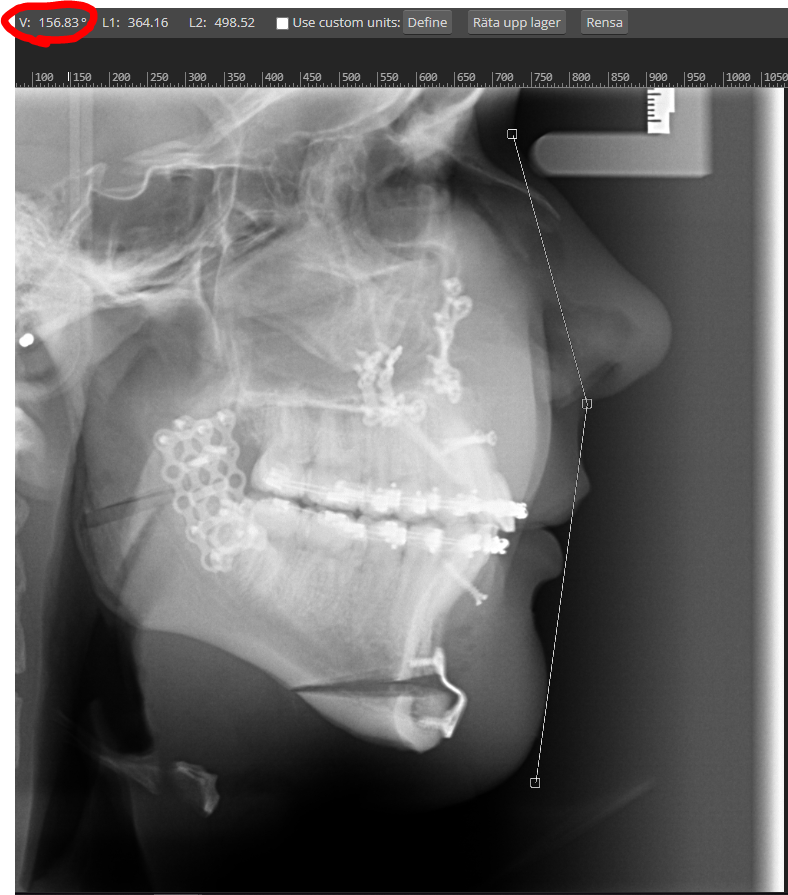

U do have bad posture looks quite like forward head postureso first of all im not, 2. whta do you think would happen to my chin if i tilted it 2 degrees lower, nigger